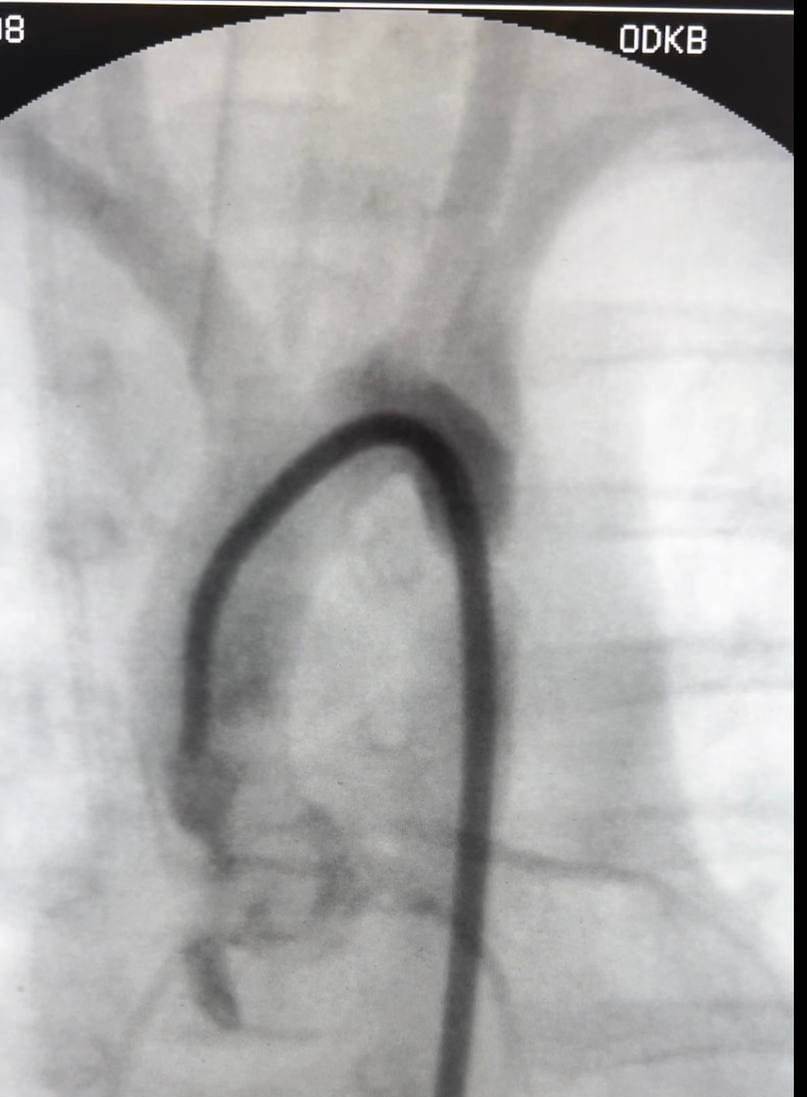

У первого ребенка с критически малым весом всего 1 кг был закрыт открытый артериальный проток, а у второй — выполнена рентгенендоваскулярная дилатация коарктации аорты.